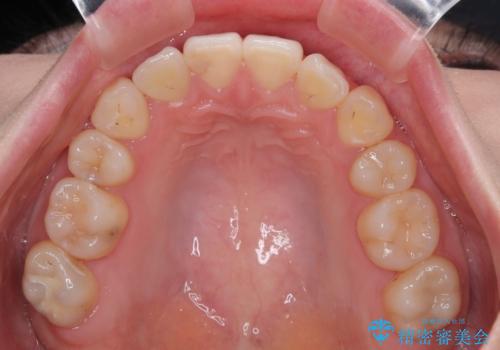

上下の八重歯とクロスバイト ワイヤー装置での抜歯矯正

20歳ということもあり、歯の移動速度が非常に速く、1年強という短期間であっという間に治療を終えることができました。

上下ともに八重歯が顕著であり、前歯のクロスバイトがあったため、上下左右の第一小臼歯4本を抜歯し、ワイヤー装置での抜歯矯正を行うこととしました。